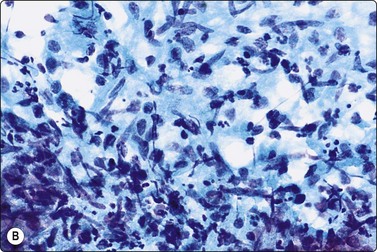

image image

Fig. 5.5 Reactive lymphadenopathy, follicular

Smear derived from reactive follicle. Centroblasts, centrocytes, small lymphocytes and tingible body macrophages with nuclear fragments (A, MGG; B, Pap; HP).

The reactive pattern is variable depending on the degree of stimulation, the number and size of germinal centers and on whether the sample derives mainly from a germinal center or from interfollicular or paracortical tissue. Germinal center material is represented by poorly defined tissue fragments composed of centroblasts, centrocytes, ‘tingible body’ macrophages (Figs 5.4, 5.5), and a number of lymphocytes which adhere to the syncytial cytoplasm (pale gray/violet in MGG) of dendritic reticulum cells (Fig. 5.6A). Dendritic reticulum cells have oval or round nuclei with a smooth nuclear membrane, a coarsely granular, uniformly distributed chromatin and small distinct nucleoli (Fig. 5.6B). The cytoplasm is dispersed in the background. A smear, which derives mainly from interfollicular tissue, consists predominantly of lymphocytes with a variable but much smaller number of scattered immunoblasts, plasma cells, non-specific histiocytes and endothelial cells (Fig. 5.7). Multiple biopsies diminish the bias caused by selective sampling.